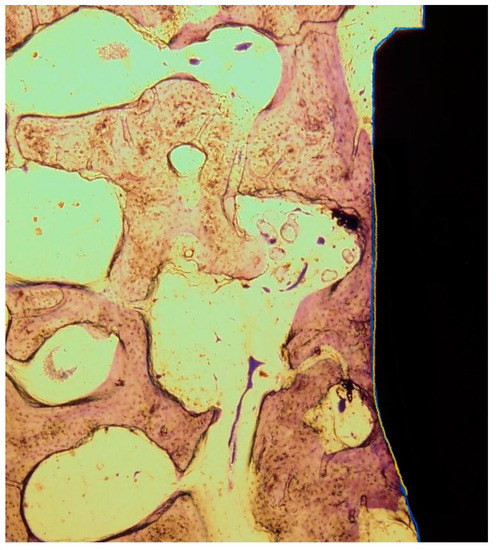

2.5. Histomorphometrical Preparation and Analysis

3.4. Histomorphometrical Evaluation